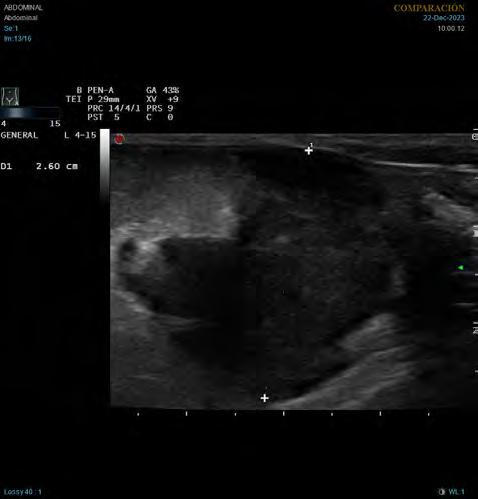

minal generalizada y una masa hipoecoica de 2,6 cm de diámetro en la zona de proyección de los linfonodos mesentéricos (Fig. 1). También se observaron hallazgos ecográficos compatibles con peritonitis, como aumento de la ecogenicidad difusa del peritoneo y presencia de líquido libre anecoico, en este caso no puncionable. Por cuestiones económicas los tutores rechazaron ampliar los análisis sanguíneos con un proteinograma. Se hospitalizó el paciente con un tratamiento inicial de amoxicilina-clavulánico (22 mg/kg/12 h/IV Amoxicilina/Ácido clavulánico Normon 1000 mg/200 mg inyectable, Normon, Madrid, España), maropitant (1 mg/kg/24 h/IV, Prevomax Dechra, Uldum, Dinamarca) y fluidoterapia (Lactato de Ringer). Para el tratamiento del dolor se le administró en infusión con-

Figura 1. Imagen ecográfica longitudinal del abdomen caudal. Masa heterogénea, principalmente hipoecoica, de 2,6 cm de diámetro, con hiperecogenicidad de la grasa adyacente.